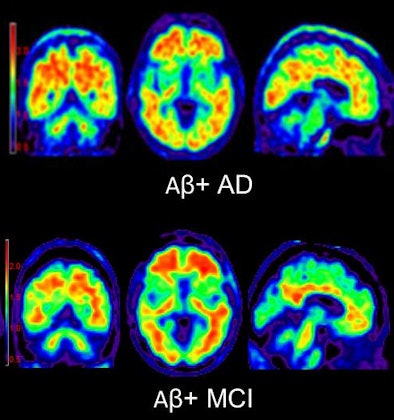

| PET images using florbetapir to highlight beta-amyloid plaque show, above, a cognitively normal subject and an amyloid-negative patient with MCI. Below is an amyloid-positive patient with Alzheimer's disease, as well as an amyloid-positive patient with MCI. All images courtesy of Neurology. |